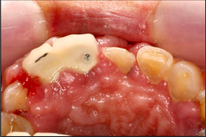

Case Background

A 65-year-old female on antihypertensives and immunosuppressants presented with severe gum swelling, inability to chew, and difficulty maintaining oral hygiene. This led to multiple decayed and periodontally compromised teeth, worsening her overall condition.

Before Treatment